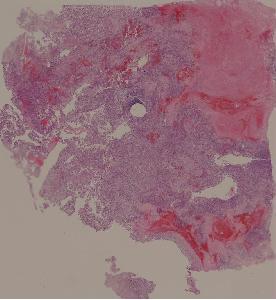

34. Osteosarcoma